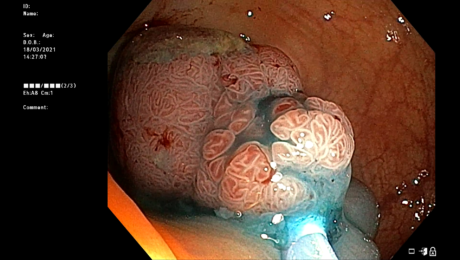

La coloscopie de dépistage

jeudi, 24 juin 2021

par Sami Boudabbous

La coloscopie La coloscopie est l’examen de dépistage le plus fiable pour mettre en évidence des lésions éventuelles au niveau du côlon. Autre avantage, les lésions détectées peuvent être enlevées partiellement ou totalement au cours de l’examen pour analyse. Le cancer colorectal (CCR) est une tumeur maligne du côlon ou du rectum. Il fait suite

- Publié dans CAS CLINIQUES, COLOSCOPIE, ENDOSCOPIE, Endoscopie interventionnelle, GASTRO-ENTÉROLOGIE